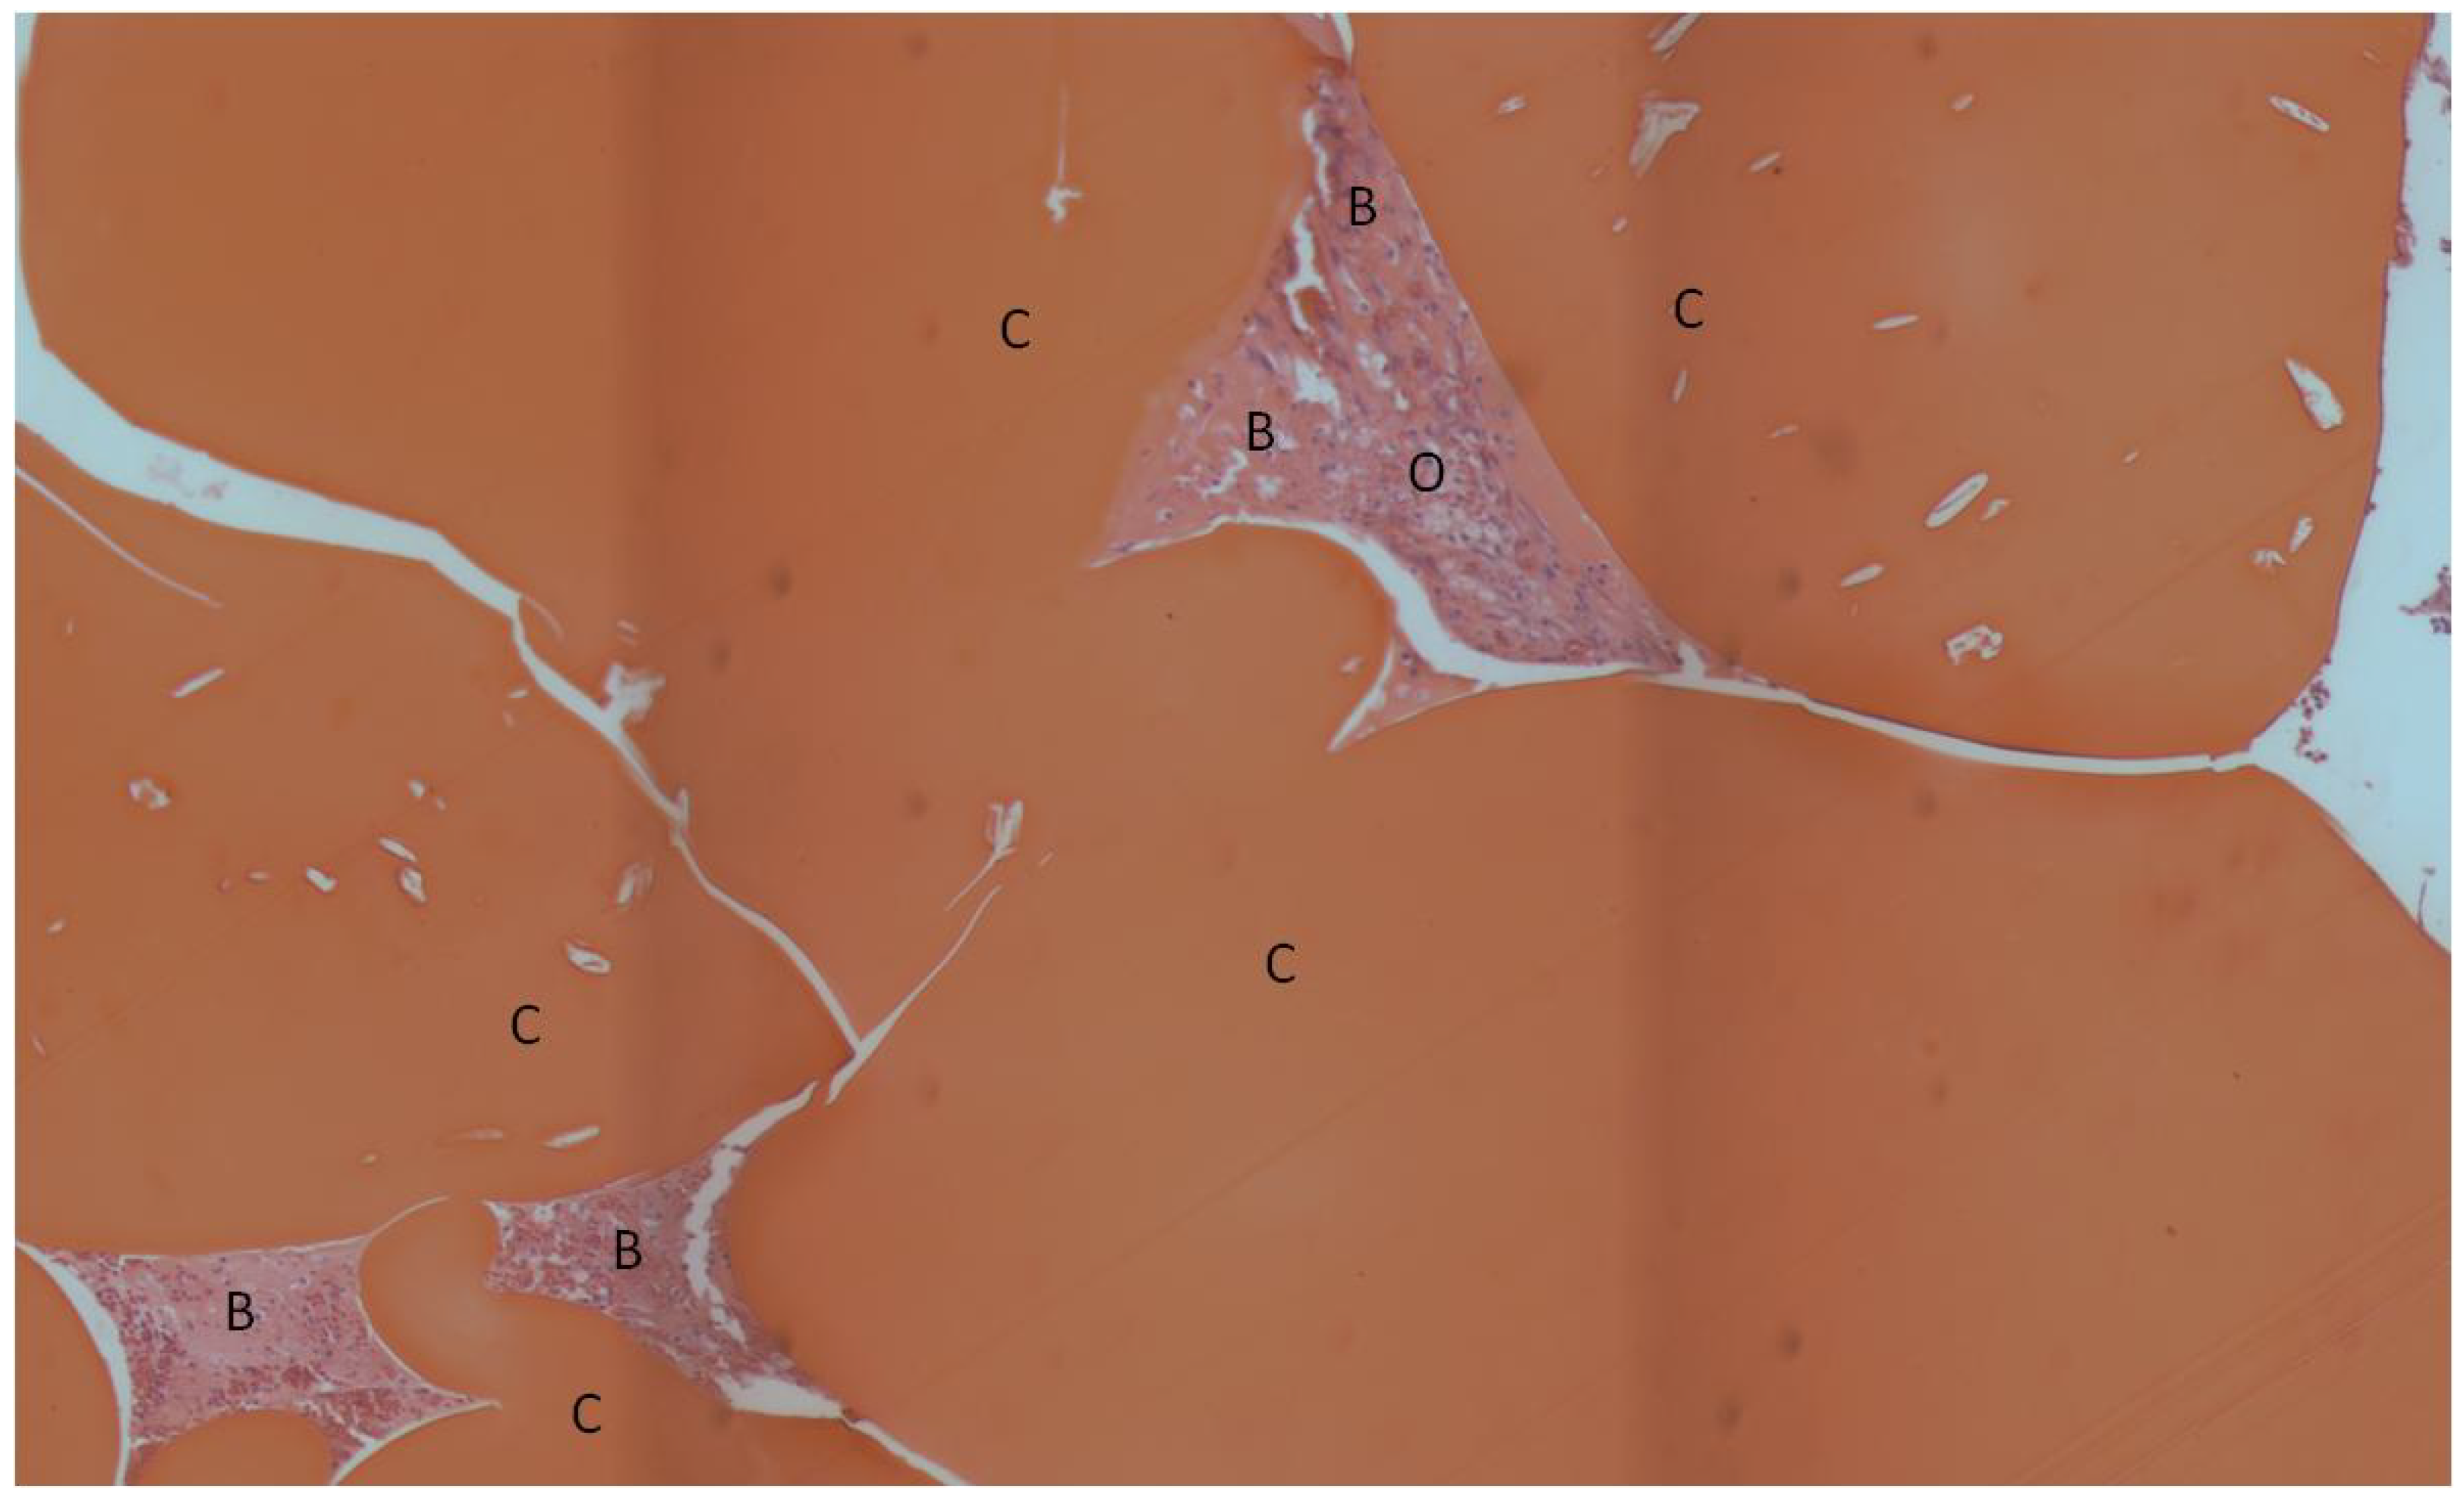

| Scaffold (%) | Osteoid (%) | Bone (%) | |

| Lyophilized (no rhBMP-2) | 65.2 ± 3.7 | 8.8 ± 2.6 | 1.8 ± 0.8 |

| Lyophilized with rhBMP-2 | 59.2 ± 6.1 | 10.4 ± 1.2 | 1.2 ± 0.3 |

| Non-lyophilized with rhBMP-2 | 71.8 ± 3.0 | 7.7 ± 2.4 | 1.0 ± 0.7 |

| Collagen Sponge with rhBMP-2 | N/A | N/A | 94.0 ± 4.4a |

| Bone Tissue Index (%) | |

|---|---|

| Lyophilized (no rhBMP-2) | 30.6 ± 8.5 |

| Lyophilized with rhBMP-2 | 28.8 ± 5.4 |

| Air-dried with rhBMP-2 | 30.5 ± 5.7 |